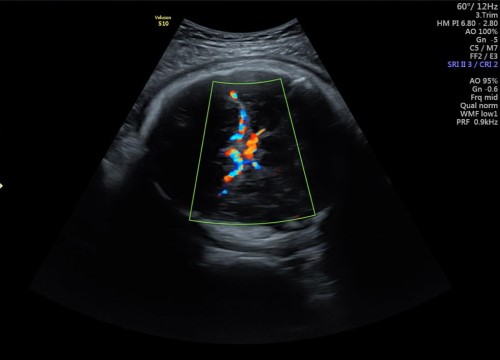

Realizamos ultrasonidos fetal avanzado desde el primer trimestre como el USG genético, USG estructural (sem 18-22) y estudios de bienestar fetal con tecnología Doppler para medición de flujos sanguíneos fetales como arteria umbilical, cerebral media, ductus venoso y en la madre las arterias uterinas.